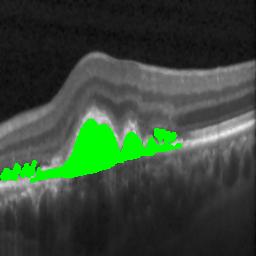

The qualitative results of the proposed system is shown in the Fig. 3. The detection task is evaluated using Area Under the Curve(AUC) metric and the segmentation task is evaluated using Dice Coefficient(DC) metric and the results are presented in Table1

| (a) De-noised OCT slice | (b)Predicted fluid region | (c)Manual fluid segmentation |

|

|

|

| (d) De-noised OCT slice | (e)Predicted fluid region | (f)Manual fluid segmentation |